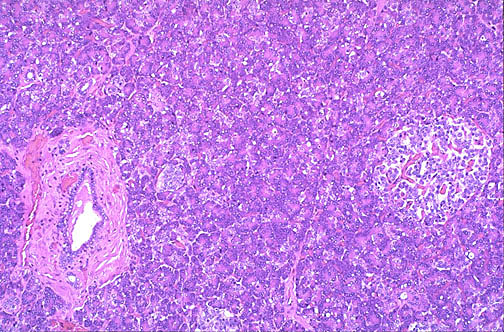

Here is normal pancreas at medium power, with a branch of the pancreatic duct at the left, surrounded by acinar tissue. An islet of Langerhans is seen at the right.